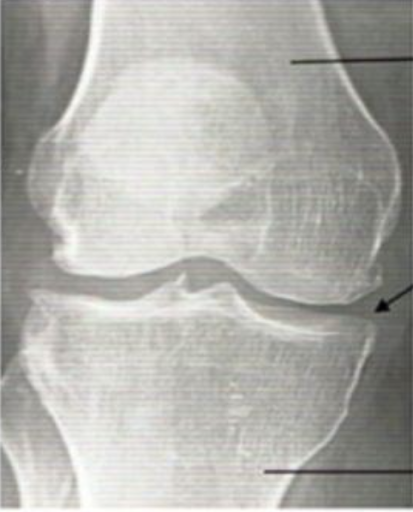

Eat this 'candy' for new knees

Published: Fri, 12/03/21